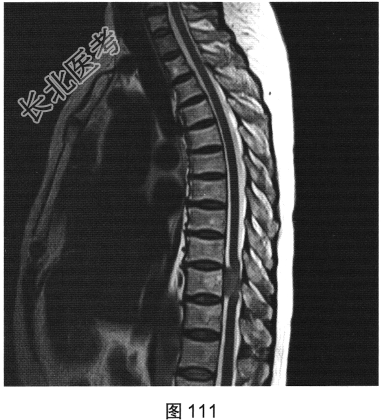

- [材料题] 患者女性,59岁,无明显诱因出现腰背部疼痛伴双下肢麻木1年,久行、久坐、久站或咳嗽、排便时疼痛加重,休息后症状缓解,1个月前腰背部麻木疼痛突发加重,行走100米既感疼痛难忍,伴双下肢无力疼痛。查体:脊柱无明显侧弯,相当于T10平面以下感觉减退,腰椎活动度受限,无紧张,棘突旁压痛、叩痛,向双下肢放射。挺腹试验阳性,跟臀试验(+),双侧直腿抬高试验(一),双下肢小腿外侧、足背感觉稍差,双侧

背伸肌肌力4级;肌张力正常,双侧巴宾斯基征可疑阳性。实验室检查:人类白细胞抗原B27阴性(一),RF<10U/ml(正常值0~15U/ml)。

- 多项选择题2.[提示]患者行MRI检查,如图111~图114所示。根据患者病史及影像学检查, 其最可能的诊断是( )